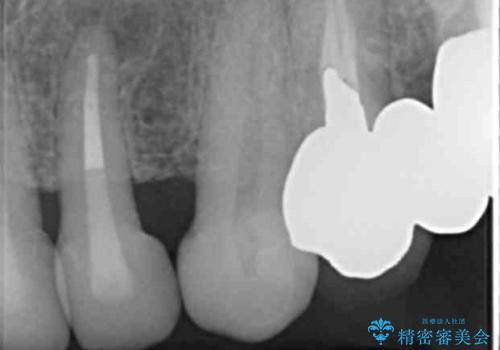

- 前歯のセラミック治療から4年半経過した患者様です。

4年ぶりに来院して下さいました。

治療した上の前歯6本は全く問題なく、「獅子舞みたいだった前歯を綺麗にして下さってありがとうございました!」と再度お礼を言って下さいました。

4年半前のクラウン装着時と変わらず、まるで天然歯のように自然に見えました。

患者様の良好なセルフケアと精密な適合の良いクラウンにより、歯肉の腫脹や退縮も認められませんでした。

4年半前に行った治療に大変ご満足頂き、他の部位の治療のため再来院して下さいました。